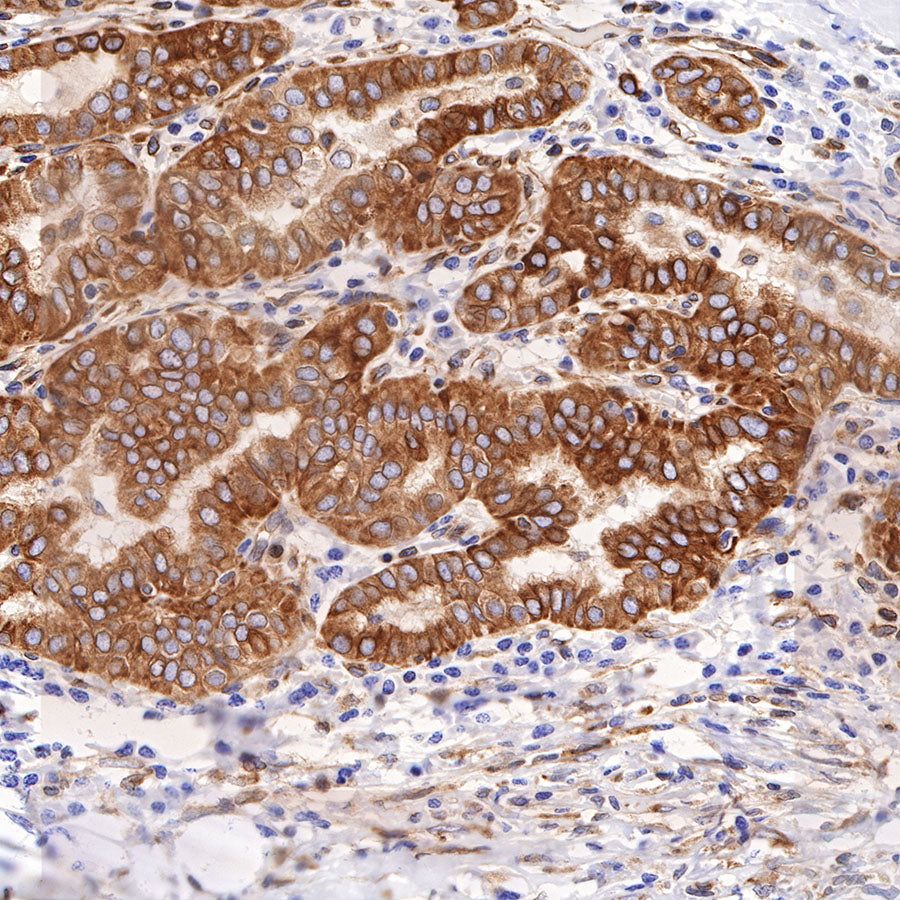

Picture

Picture

Immunohistochemistry